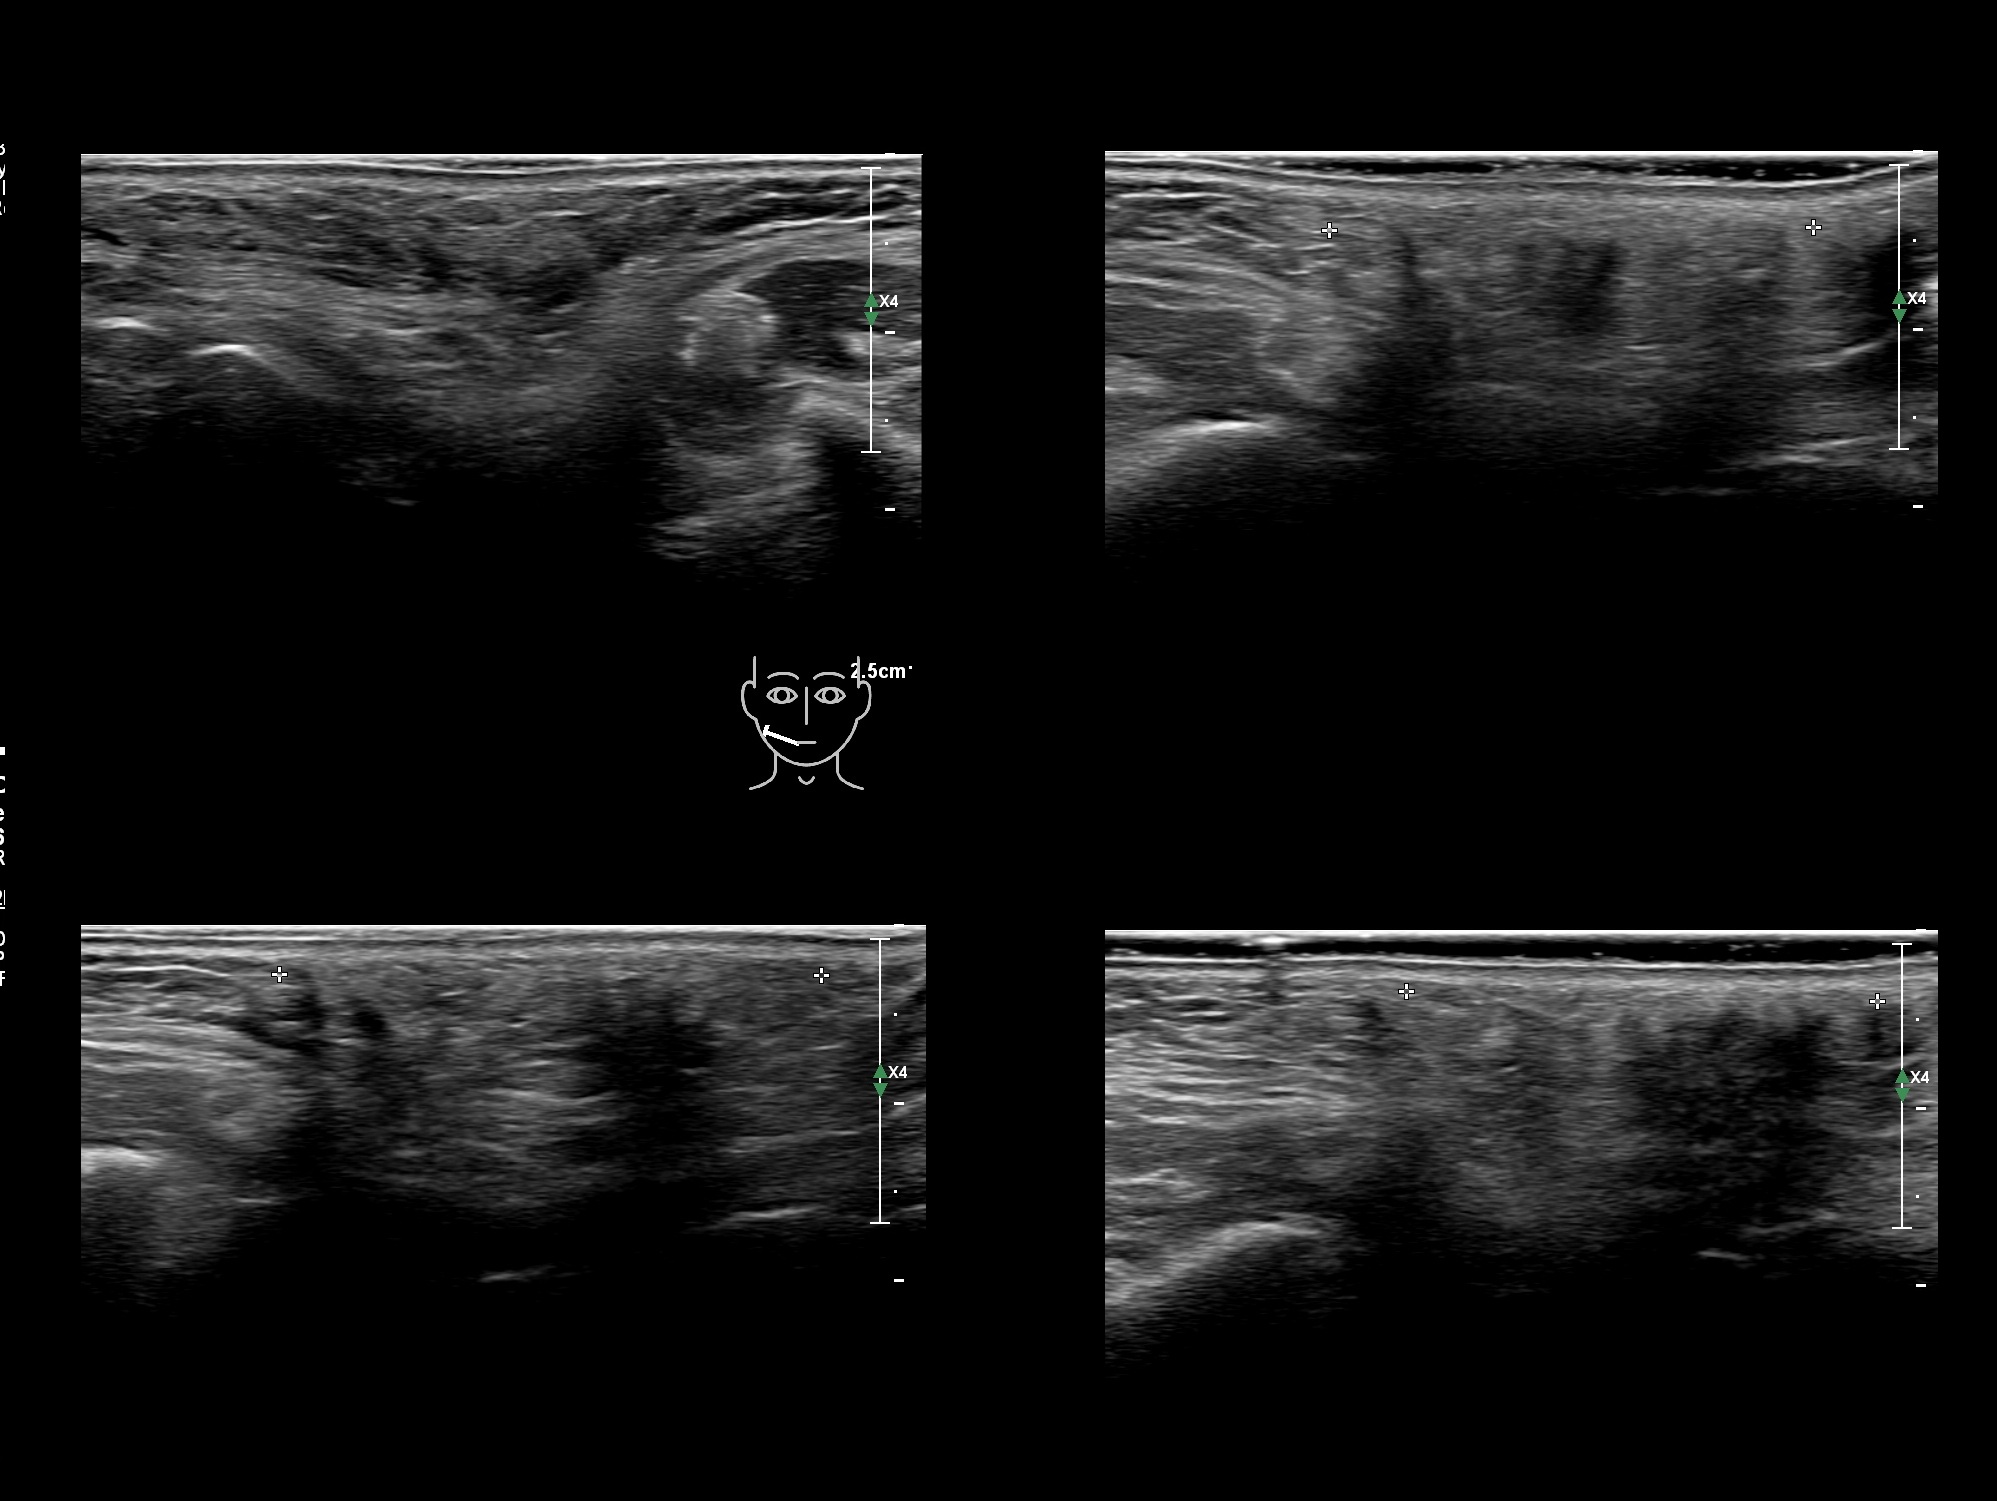

Fillers

Draw in the second image below where the fillers are located. To check if your answer is correct, swipe the first image to the right.